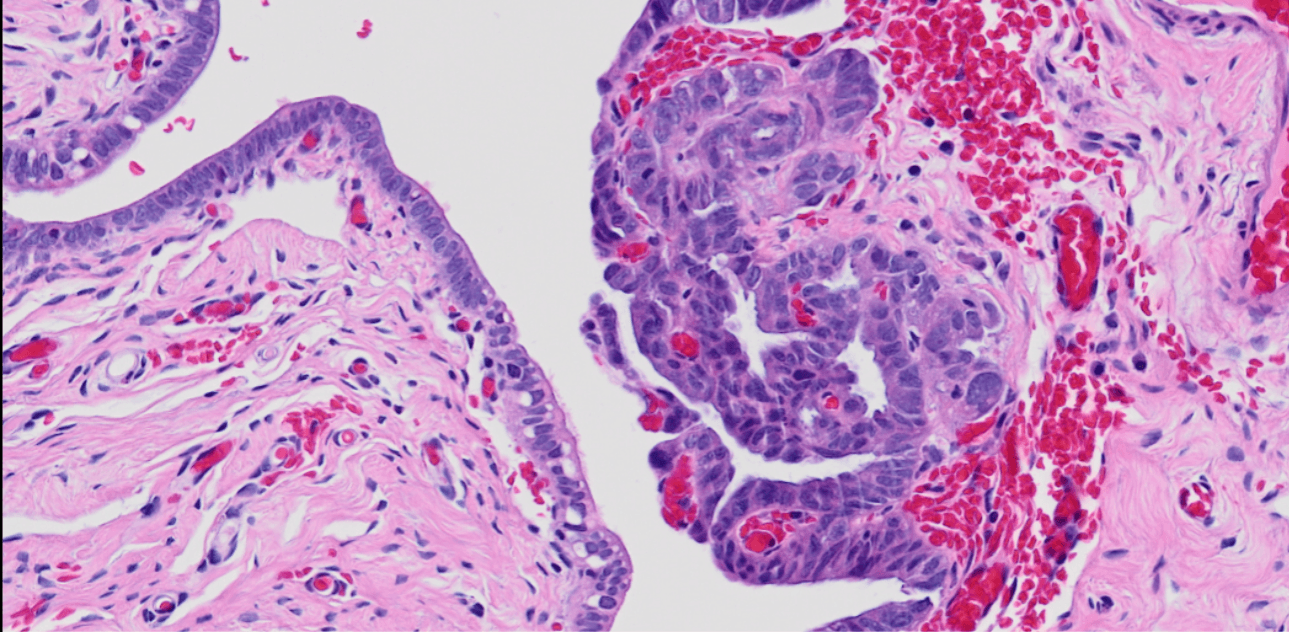

Project award

This study aims to create machine learning tools that will analyse histopathological information with genetic signatures known to be correlated with poor outcomes. This will help to determine if the lesions have the potential to become aggressive cancer.

Project leads: Rajan Kulkarni, Amaya Viros

Collaborating institutions: OHSU, University of Manchester